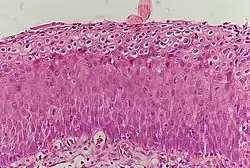

Classification

_normal_squamous_epithelium.jpg)

Historiquement, les modifications anormales des cellules épithéliales cervicales étaient décrites comme une dysplasie épithéliale légère, modérée ou sévère. En 1988, l'Institut national du cancer a développé le « Système Bethesda pour la notification des diagnostics cytologiques cervicaux/vaginaux »[12]. Ce système fournit une manière uniforme de décrire les cellules épithéliales anormales et de déterminer la qualité des échantillons, fournissant ainsi des conseils clairs pour la gestion clinique. Ces anomalies ont été classées comme squameuses ou glandulaires, puis classées en fonction du stade de la dysplasie : cellules atypiques, légères, modérées, sévères et carcinomes[13].

En fonction de plusieurs facteurs et de l'emplacement de la lésion, la NCI peut débuter à partir de n'importe laquelle des trois stades et peut ensuite progresser ou régresser[1]. Le grade de la lésion intraépithéliale squameuse peut varier.